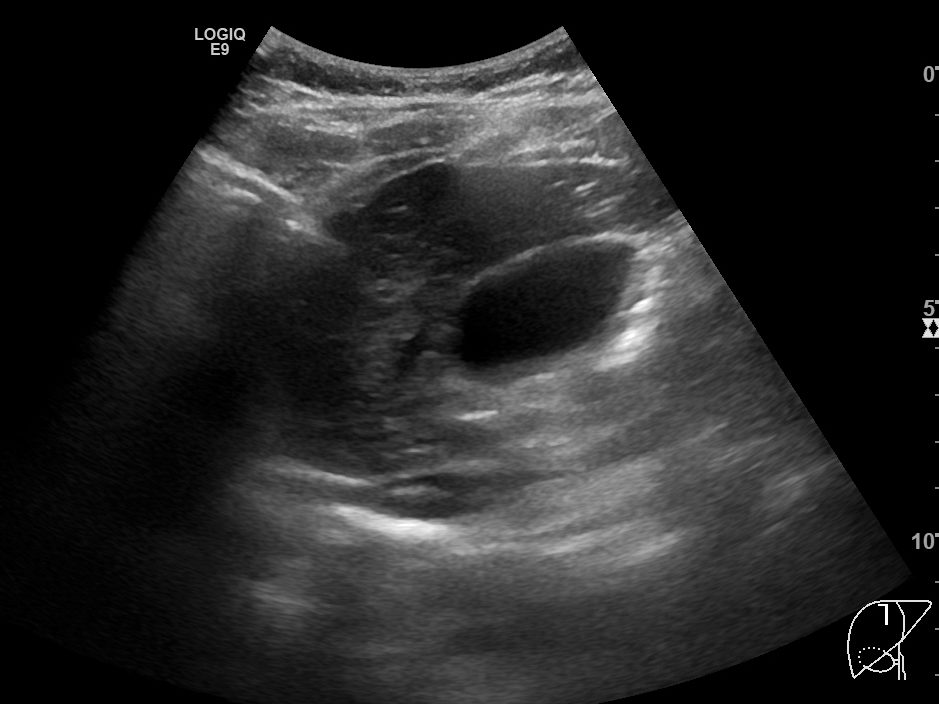

다음으로 중간정맥(middle hepatic vein)의 B모드 및 컬러도플러영상입니다. 컬러도플러영상에서 또렷하게 보이는 중간정맥이 B모드영상에서는 마찬가지로 매우 가늘고 희미하게 보입니다. 컬러도플러 영상에서 보여주는 중간정맥의 굵기가 실제 직경과는 차이가 있겠으나, B모드에서 보이는 것보다는 훨씬 직경이 클 것으로 보이며, B모드영상에서는 전혀 확인할 수 없었던 가지부분들도 컬러도플러영상에서는 또렷하게 확인됩니다.

B모드영상에서 간정맥이 실제보다 훨씬 얇고 희미하게 보이거나, 아예 잘 보이지 않는 이유는 간정맥의 혈관벽이 얇아서 초음파신호가 반사되지 않아 영상에서 혈관벽을 특정할 수 없기 때문입니다. 특히 간실질의 에코음영이 거칠거나 간섬유화가 심하게 진행된 만성 간질환 환자들에서 간정맥을 확인하지 못하거나, 굉장히 가늘게 보이는 경우가 많습니다.

사실, 간정맥이 가늘고 수축되어보인다고 해서 특정한 질환의 가능성을 의심해야 하는 상황은 거의 없습니다. 간정맥이 크게 늘어나는 울혈성 심부전증이나 간정맥 내 혈전이나 막을 확인할 수 있는 버드-키아리 증후군 등과 달리, 간정맥의 수축이 특정질환의 특징적인 소견으로 지목되지는 않기 때문이지요. 하지만, 간정맥과 같이 엄연한 해부학적 구조물조차 제대로 확인하기가 어려워진다면 간초음파의 영상 질에 대한 확신이 어려워질수도 있을겁니다.